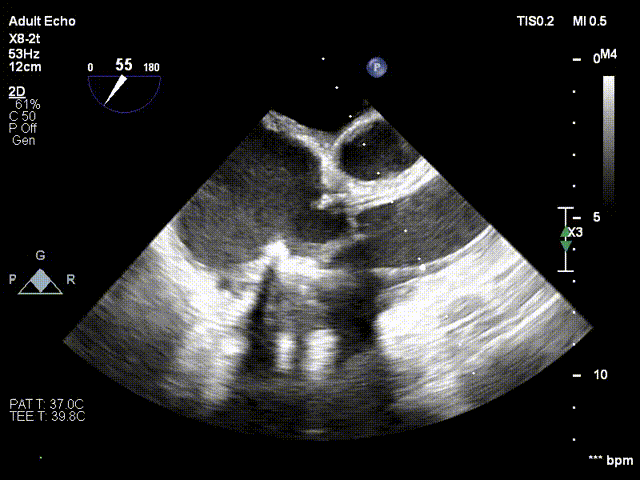

食道超声引导瓣膜跨瓣定位

术后食道超声显示球扩瓣形态理想、反流消失